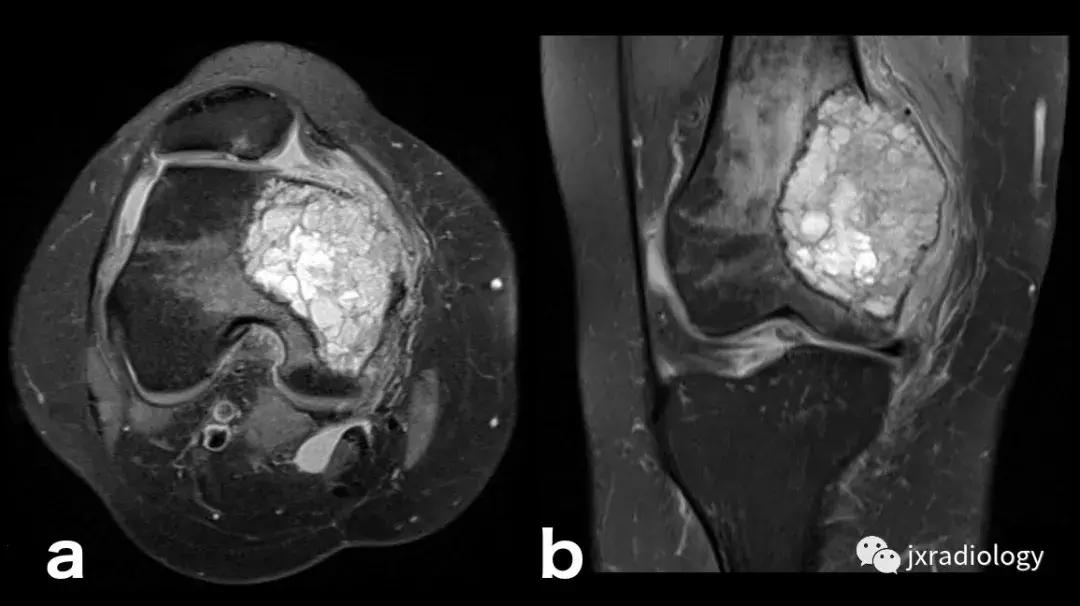

图22:骨肉瘤(a,b:冠状和轴向PD-FS-WI):肿瘤性水肿继发于骨小梁破坏引起的直接毛细血管损伤,并伴有血管内液体释放和出血。区分周围水肿和肿瘤侵袭可能是困难的。

图23:骨巨细胞瘤(PD-FS-WI):也存在肿瘤性骨髓水肿。